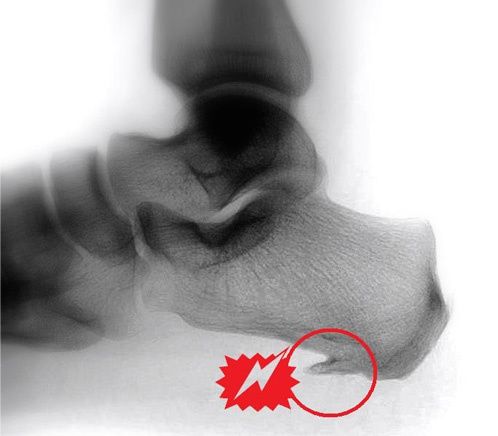

Die klinische Untersuchung ist für die genaue Diagnose unentbehrlich. Eine seitliche Rön

tgenaufnahme des Fußes bestätigt dann meistens den Verdacht des Arztes. Die Ursache liegt nämlich häufig in einem so genannten „Fersensporn“…

Der plantare Fersensporn kann auch ein Zufallsbefund auf dem Röntgen sein, ohne dass der Patient Schmerzen hat. Wenn Schmerzen vorhanden sind, dann spricht das für eine Entzündungsreaktion im Bereich des Sporns. Diese Entzündung nennt man „Plantarfasziitis“.